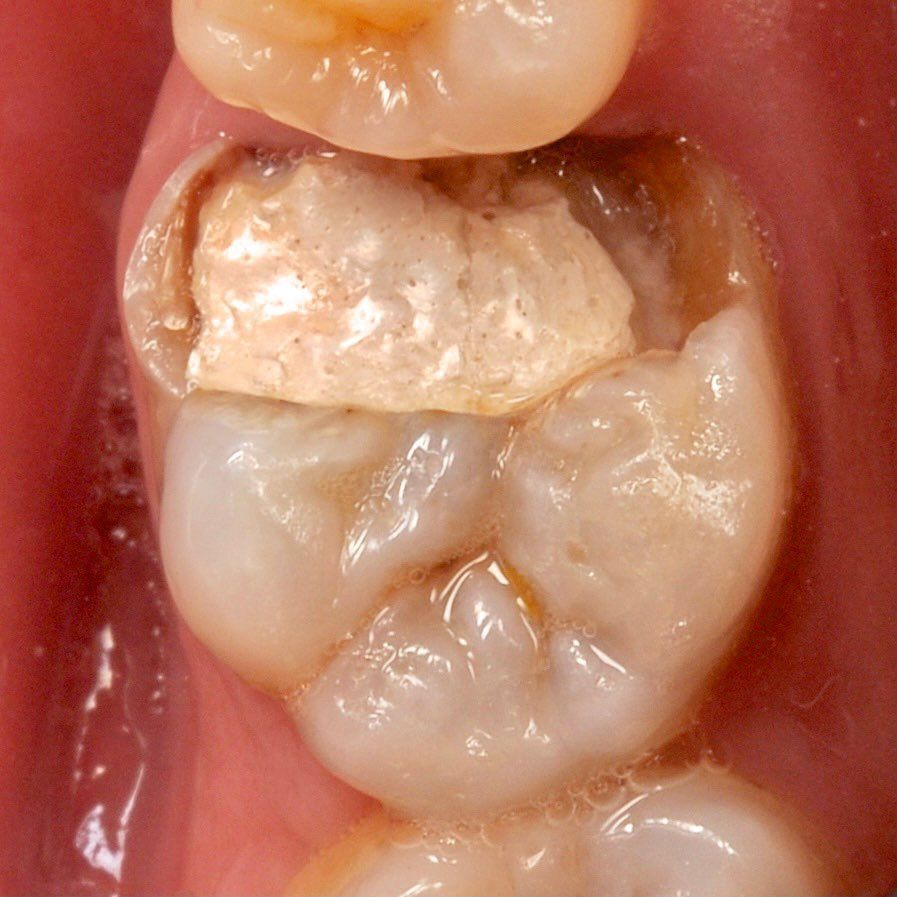

укрепление зуба стекловолокном

Создаем прочную основу внутри зуба

укрепление зуба